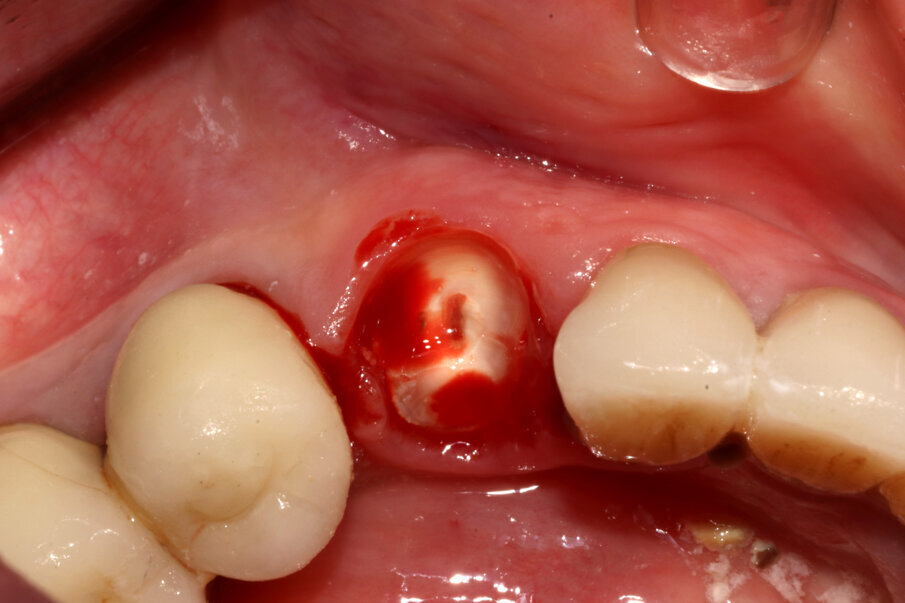

Nature” proposto dalla SISS (Figg. 5-7), che sostanzialmente prevede una decoronazione dell’elemento dentario e un trattamento della radice secondo una direzione crown-down: il canale viene svuotato, la radice raccordata al margine osseo vestibolare, e sezionata in modo da comprendere nella componente rimossa anche l’apice radicolare oltre che la porzione linguale della radice affetta da riassorbimento radicolare. Rimane così una piccola quota di radice vestibolare, spessa circa 1 mm e lunga circa 6 mm, con forma a “C” (per mantenere il legamento parodontale fino ai picchi ossei e mantenere così le papille interdentali). A questo punto viene inserito un impianto Nobel Active 4,3 x 13. Il controllo del posizionamento implantare in ossequio al progetto protesico viene eseguito grazie a un sistema di Chirurgia Navigata (X-Guide, X-Nav Technologies) che ci consente di ottenere una deviazione finale di soli 0,2° (Fig. 8). Una volta inserito l’impianto, lo stesso viene collegato a una torretta provvisoria in titanio sulla quale viene costruito un provvisorio intraoperatorio che rispetti il tragitto transmucoso e non eserciti forze compressive o dislocanti sullo shield vestibolare.

Figg. 9-11_Inserimento dell’impianto e costruzione di una corona provvisoria. Si noti la forma a “C” dello shield e, al termine dell’intervento, la compostezza dei tessuti, gestiti senza alcun tipo di lembo.

Fig. 12_La porzione di radice linguale correttamente asportata compresa di apice radicolare.